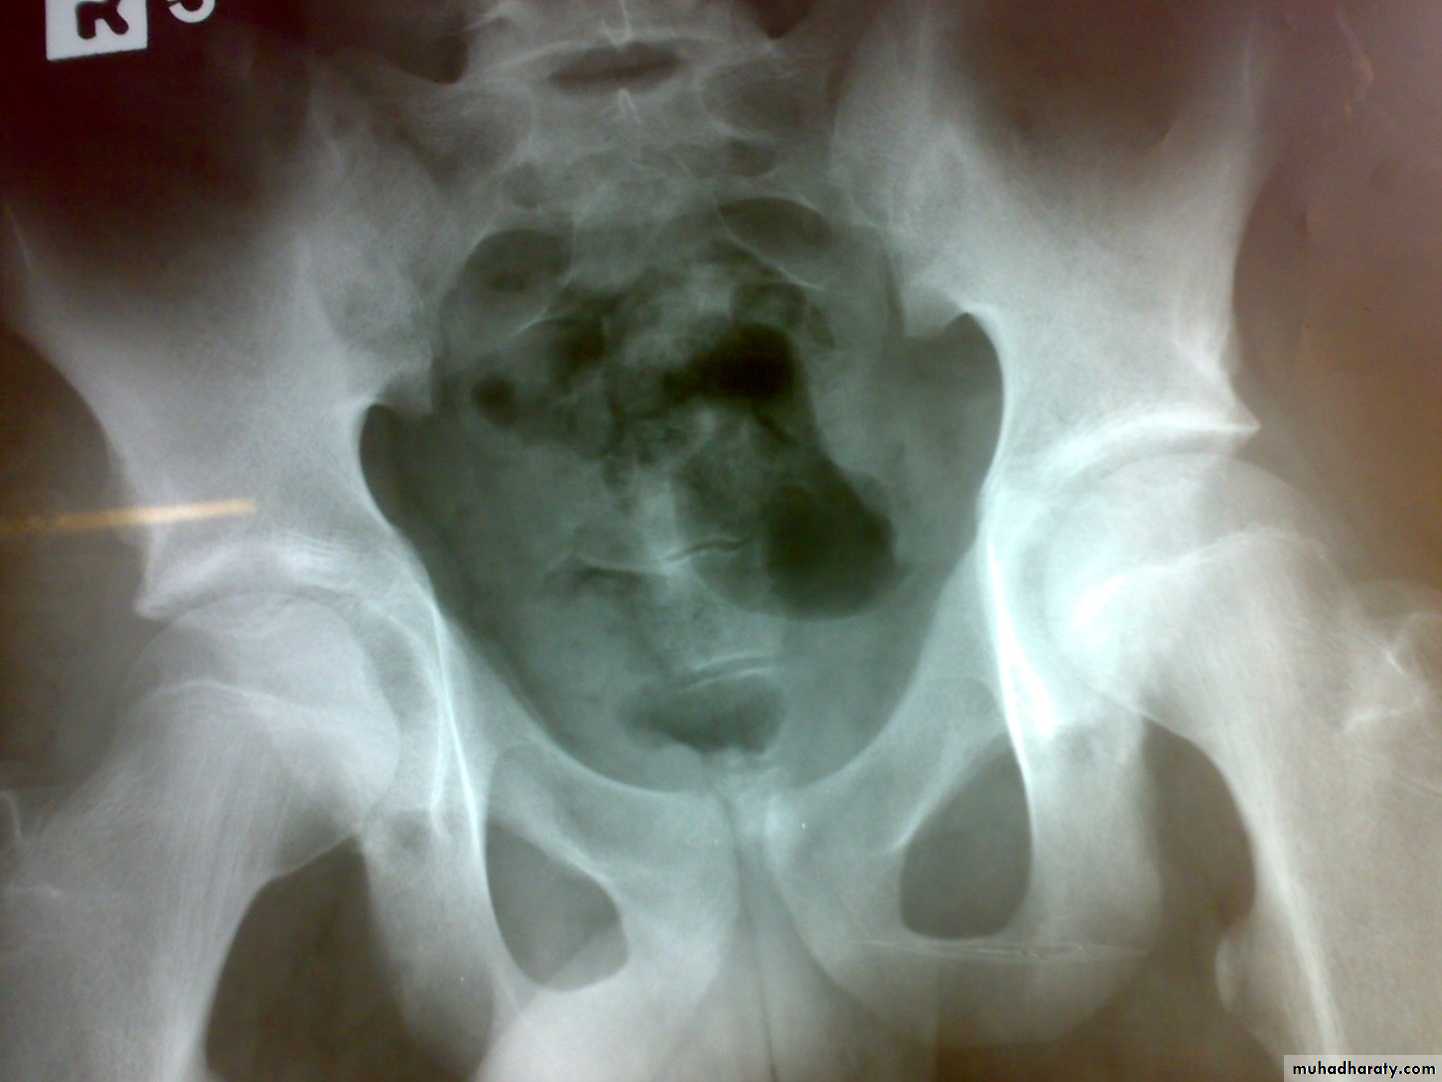

Hydatid disease of bone

Hydatid disease affect bone in 1-2%.

The cyst slowly enlarged in bone with little respect to cortical or epiphyeseal boundaries.

The bones most commonly affected are the vertebrae, pelvis, femur, scapula and ribs.

Patiens may complain of pain and swelling or pathological fractures.

It most differentiated from benign and malignant bone tumors.

Treatment by radical resection if possible with prolonged courses of albendazole.